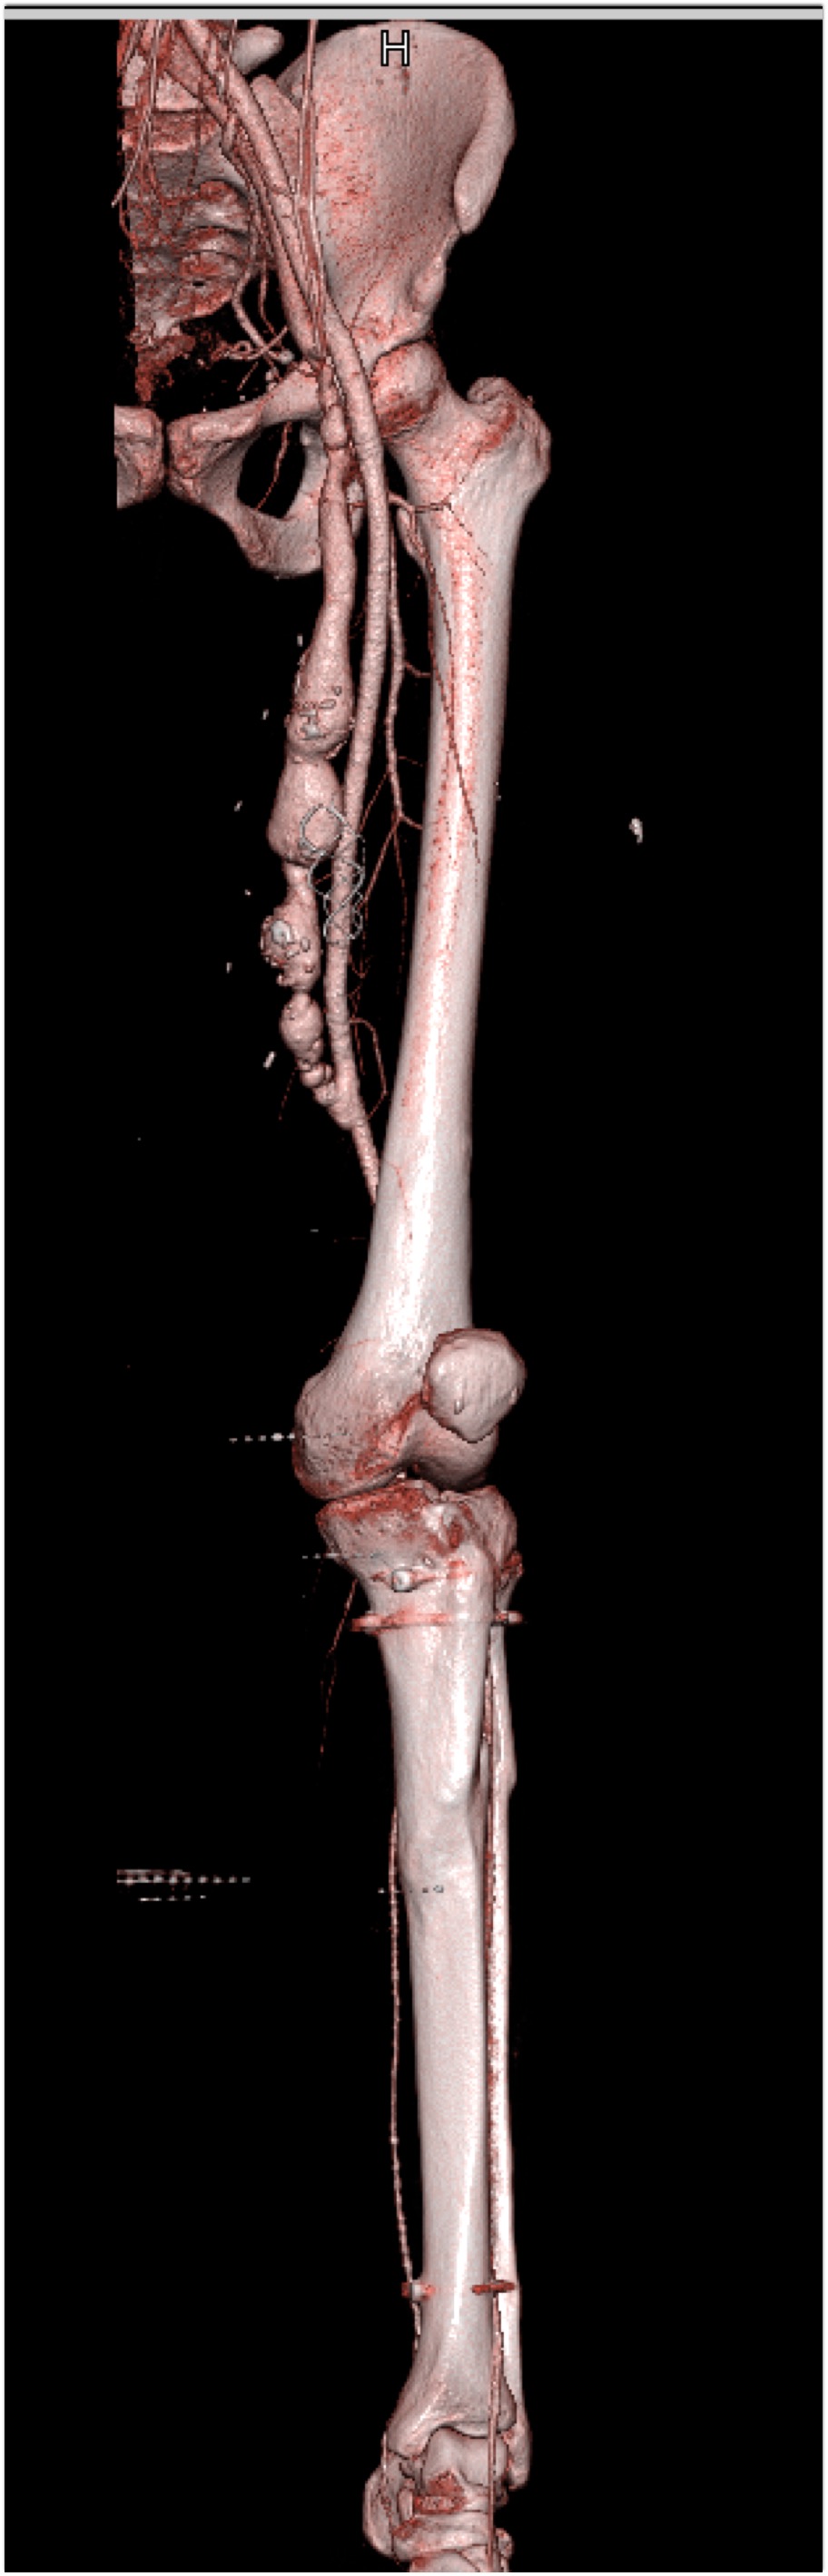

2) In this patient on dialysis for ESRD the best diagnosis is?

normal bypass graft

AV fistulae with aneurysms

vasculitis

infectious vascular disease